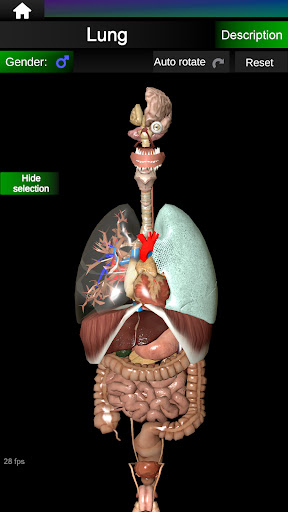

* Дихальна система, яка включає трахею, бронхи, легені та анімацію цієї системи.

* Легкий доступ і навігація (масштабування, 3D-обертання).

* Приховати або показати інформацію.

* Порівняйте чоловічі та жіночі органи.